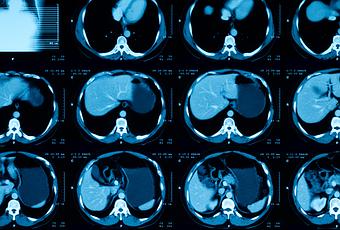

Le carcinome urothélial représente environ 90% des cancers de la vessie et son incidence est d'environ 70.000 nouveaux cas entraînant 17.000 décès par an aux États-Unis. Lorsqu’il est avancé, le carcinome urothélial est inopérable et est normalement traité avec des médicaments de chimiothérapie à base de platine, tels que le cisplatine ou le carboplatine, et/ou des médicaments inhibiteurs de point de contrôle immunitaire qui visent à libérer les capacités anticancéreuses du système immunitaire. Mais dans la plupart des cas, ces traitements fonctionnent pendant une période limitée avant que la maladie ne se remette à progresser.

L’essai a testé le médicament chez 113 patients atteints d'un carcinome urothélial avancé, traités dans 42 sites à travers le monde. Les patients ont reçu des perfusions de SG 2 fois toutes les 3 semaines. Le traitement était arrêté si les tumeurs se développaient (progressaient) ou si les effets secondaires devenaient inacceptables. Ces participants avaient vu leur cancer progresser en dépit d’une chimiothérapie à base de platine et d’un traitement par inhibiteurs de point de contrôle stimulant le système immunitaire. Le traitement par SG permet ici :